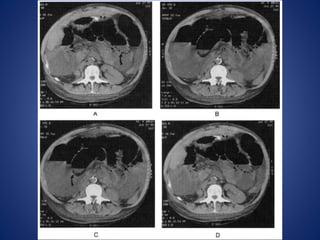

CT scan

• CT scan examination is

particularly useful in

patient with a history of

abdominal malignancy, in

postsurgical patients, and

in patient who have no

history of abdominal

surgery and present with

symptoms of bowel

obstruction.